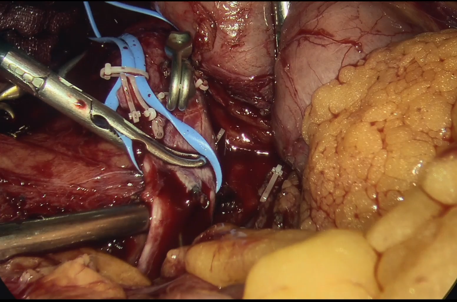

图为:全麻下开腹下腔静脉切开滤器取出术